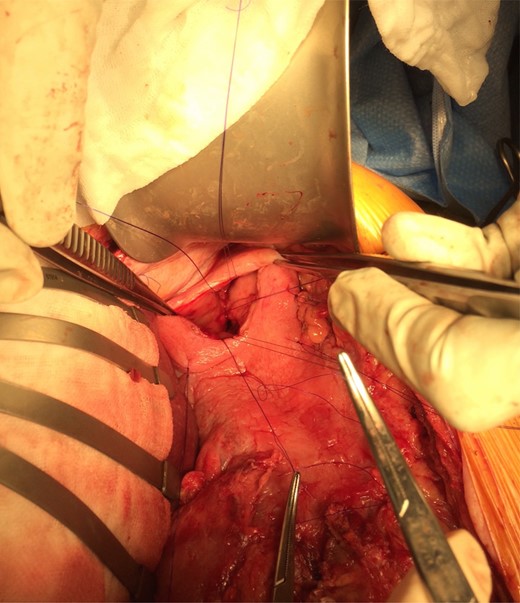

Gastroscopy the following day showed a fundal gastric ulcer and the MWT, which was now larger and deeper (Fig. 2). On Day 10, the patient underwent surgery. A midline laparotomy incision was performed, followed by extensive adhesiolysis. After the anterior wall of the stomach was exposed from the GEJ to pylorus, a longitudinal gastrotomy was created over the fundus. There was a deep MWT at GEJ extending along the greater curve of the stomach, which was bleeding actively. The MWT was oversewn with interrupted 3/0 PDS sutures and hemostasis achieved. A second, larger fundal ulcer, presumably from pressure necrosis of SB tube, was also noted. This ulcer occupied most of the fundus of stomach, which was excluded from the gastric cavity, by the closure of fundus with interrupted 3/0 PDS (Fig. 3). Postoperatively, oral fluids were commenced on Day 12. On Day 15, a Gastrografin swallow study was normal, and oral intake was encouraged. The patient recovered without complications and returned to the rehabilitation facility.

The gastric ulcer was excluded from the rest of the stomach through gastrostomy using 3/0 PDS suture.